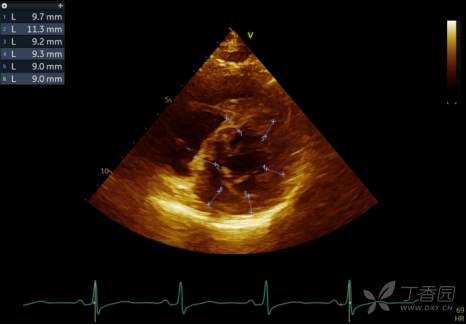

2022-08-02查心脏超声提示:室间隔基底部局限稍增厚,较厚处约13mm,SAM(+),左室流出道内流速增快,约3.99m/s,流出道最大压差约64mmHg,平均压差约31mmHg。二尖瓣中度反流。